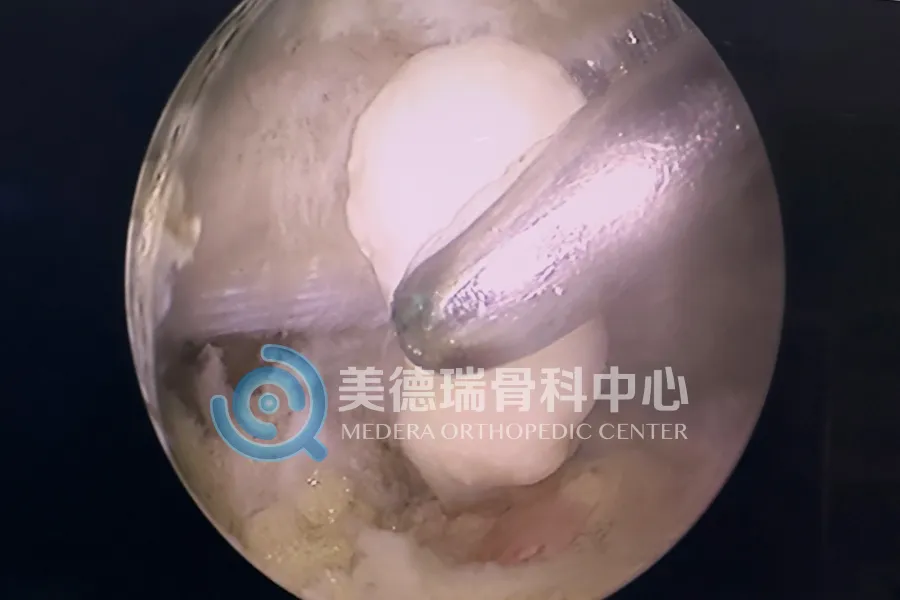

经过细致的查体与影像学评估,病因最终被锁定:一枚游离体卡在了髁间窝及后关节囊的深处,正是它构成了关节伸直的物理性阻挡。

因为这枚游离体的位置太过“刁钻”。它躲在膝关节的后室,这里是常规关节镜手术的“视野盲区”,更是操作的“险滩”——狭小的空间紧邻腘窝的血管和神经束。在这样的位置进行手术,不仅需要精湛的技术,更需要极强的风险把控能力。

依托美德瑞骨科医生集团成熟的微创技术体系,张威医生专家团队为患者实施了关节镜下经后内侧入路游离体取出术。这一术式避开了大面积切开,在保护周围血管神经的前提下,通过微创通道直达关节后室,精准移除了那枚长期卡压关节的游离体。